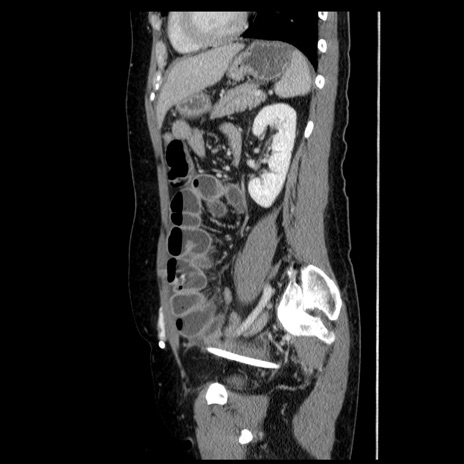

症例6(矢状断像)

【症例】50歳代女性

【主訴】下腹部痛

【現病歴】本日朝より下痢2回あり。 昼食を食べた後、嘔吐3回、下腹部痛認め、症状軽快せず、当院救急搬送。

最終食事:本日昼(生ものなし)。 昨日の夜、刺身を食ぺたとのこと。周囲に同様の症状の者なし。普段、排便は毎日あるとのこと。

【既往歴】卵巣癌術後(8年前に当院で卵巣摘出)

【身体所見】 意識清明、腹部:平坦、腸蠕動音→、やや硬、下腹部自発痛・圧痛あり、反跳痛あり、筋性防御なし。

【データ】WBC 16000、CRP 0.01